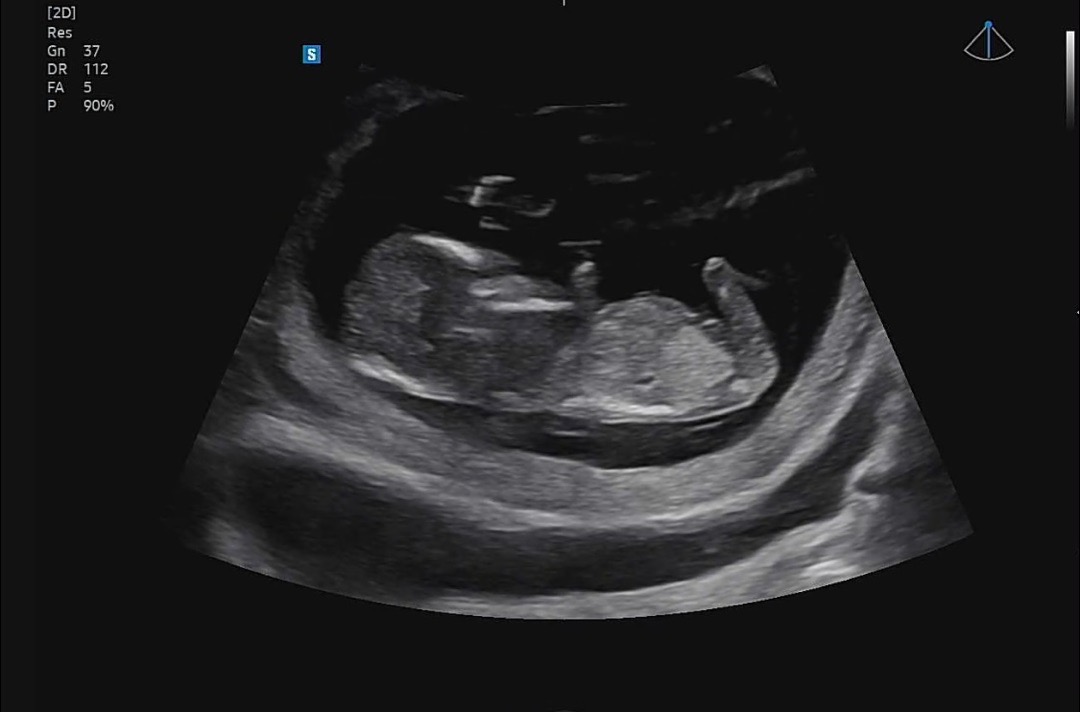

12주차 각도법

다들 의견 부탁드려용 :)

척추랑 생식기부분 각도가 보여야맞춰보는데 다리가 가리고있어요ㅎ